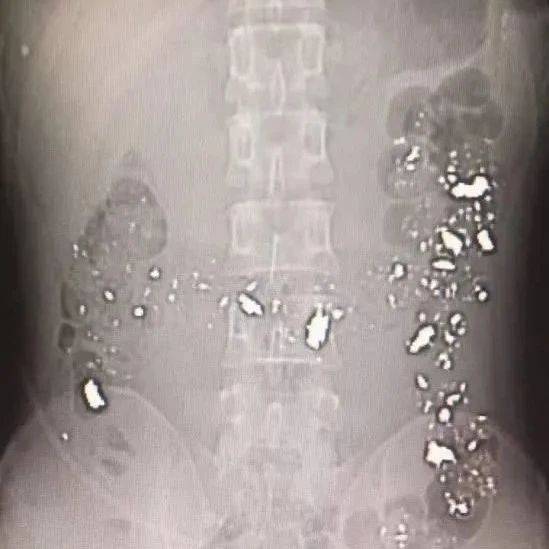

腹部CT片